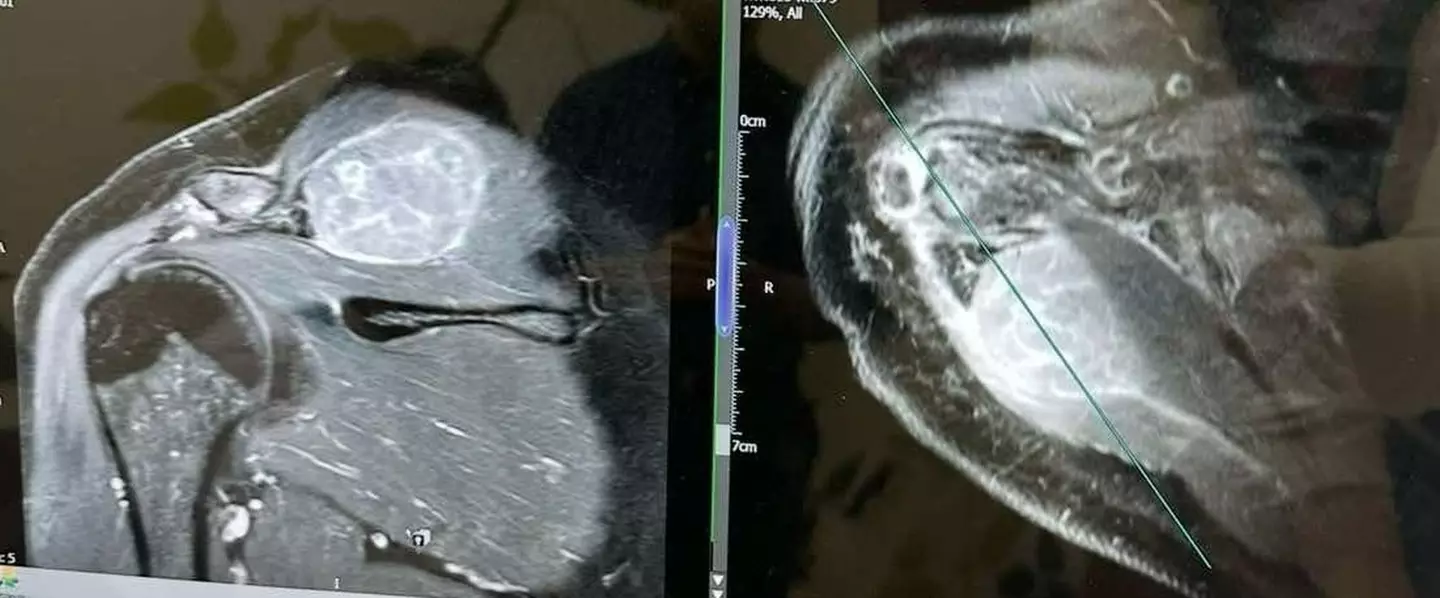

After speaking with the doctor Claire was told that shoulder injuries can 'take a while to heal', but she was referred to an orthopaedic consultant and underwent on MRI scan.

She faced a tough wait over Christmas 2023, finding herself in 'Google rabbit holes' as she tried to figure out what could be wrong, and on January 26 she got her diagnosis: stage four cutaneous malignant melanoma.

A devastating stage four cutaneous malignant melanoma diagnosis